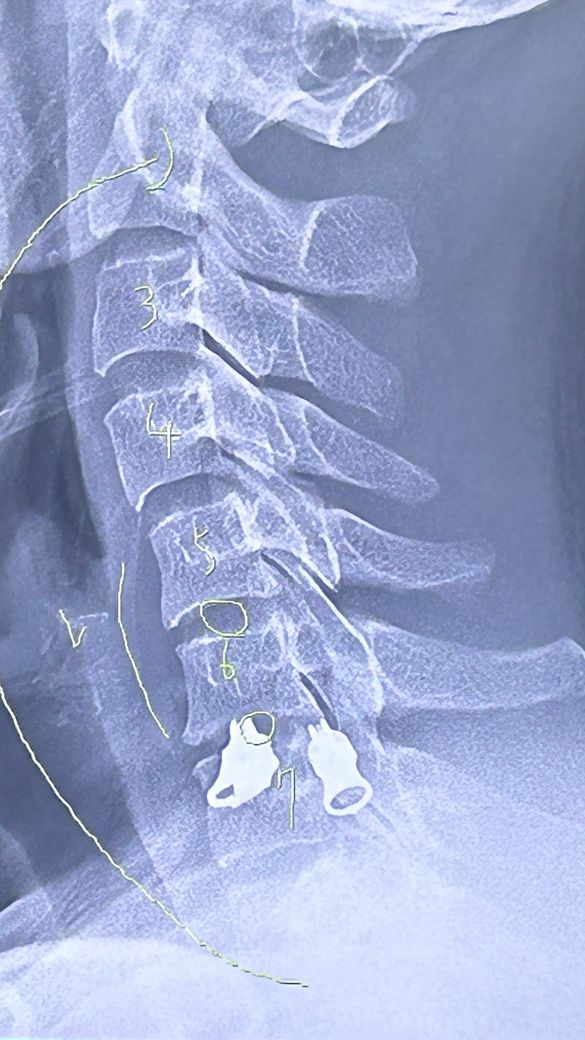

목디스크 일자목이 있다고 하는데 시술이 필요한지 알려주세요

목과 팔 통증이 심해 정형외과에 방문해 씨티촬영을 했고 이후부터 두어달간 물리치료 및 주사치료를 이어오고 있습니다. 여전히 상태가 그대로이며 손가락(두번째,세번째 손가락)저림 현상까지 있습니다.

1. 시술이 필요한 정도인가요?

2. 비용은 어느정도 할까요?(평균적으로)

3. 시술 후에 손가락 및 팔통증도 사라지나요?

• 1번 째 사진